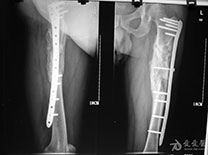

7术后遵医嘱可扶拐下地行走,患肢不能负重。骨折愈合后可弃拐行走。